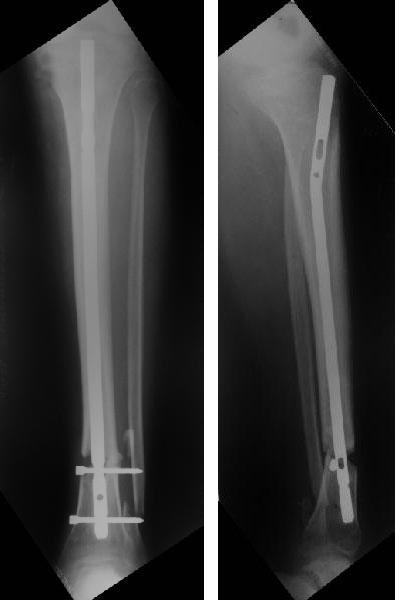

У молодого человека, у которого еще есть перелом тела поясничного позвонка, выполнен синтез голени.

Ротационная подвижность пока устраняется дополнительной гипсовой лонгетой.Из двух вопросов "кто виноват" и "что делать" предлагаю ответить на второй. Мое предложение:удалить гвоздь, наложить аппарат, добиться репозиции,забить этот же гвоздь, на этот раз с блокированием через отверстия гвоздя.Кроме моего высказаны следующие предолжения:1) заблокировать как есть нижние отверстия;2) наложить снаружи аппарат для стабилизации, в таком виде ждать сращения;3) перейти на лечение аппартом;4) перейти на лечение гипсовой лонгетой, так как все-равно перолом позвоночника-месяц лежать. Ваше мнение? Спасибо. Снимки в архиве.

Здравствуйте коллега! Интересный случай! Буквально 3-4 месяца назад столкнулся с подобной ситуацией. Плюс у больного имелась нейропатия малоберцового нерва, стойкая эквинусная деформация стопы. Молодой человек лечился в другом лечебном учреждении. Первым этапом выполнено удаление стержня ChM, наложен аппарат внешней фиксации, в течении недели проводилось устранение имеющихся деформаций. Вторым этапом выполнен ЗИМО стержнем MetaDiaFix-T большего диаметра (картинки в приложении).